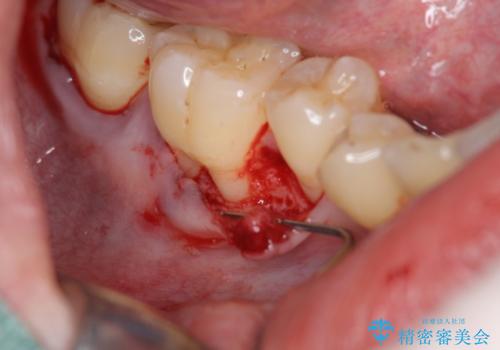

- 定期的にクリーニングに通われている中、右下の歯がどんどん染みるようになってきていることの改善を希望されました。

元々歯ブラシの圧が強く、歯が削れてしまい歯ぐきも下がってしまっている状態です。

数ヶ月知覚過敏薬を塗布し続けましたが改善見られず、下がってしまった歯ぐきを移植により改善する治療計画をたてます。